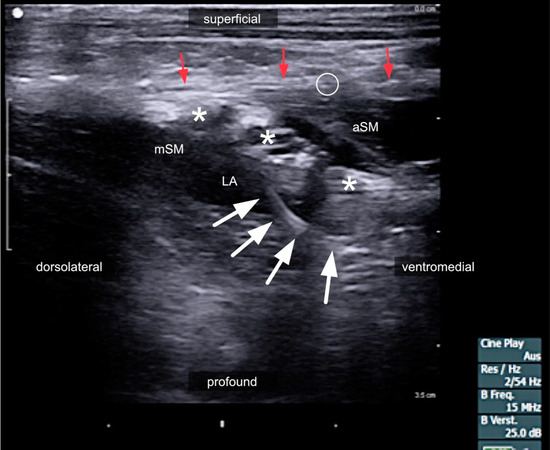

3.2. Interscalene Access

3.3. The Risks of Interscalene Catheters

3.6. The Role of Ultrasound